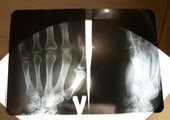

- Утром 20 декабря я вышел из дома и спустился к крытой парковке. Как только я зашел внутрь, на меня напал мужчина, который ударом ноги сломал мне кисть левой руки. Затем он убежал, вероятно, услышав шаги приближающихся людей. В тот же день, выйдя из травмпункта, я написал заявление на имя начальника отдела полиции № 1 УВМД по Владивостоку, - рассказал подробности Николай Кочетков.

Фото: РИА PrimaMedia